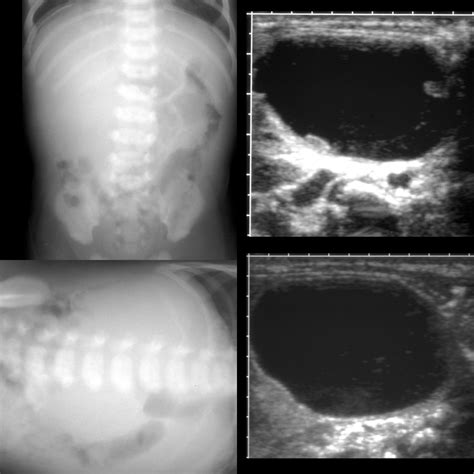

Ultrasound Non-invasive imaging to view soft tissues and identify fluid-filled cysts.

Because the abdomen contains a dense arrangement of structures, relying on a physical "self-exam" is rarely sufficient. A doctor will typically correlate physical findings with diagnostic imaging. For instance, an ultrasound might distinguish between a solid tumor and a fluid-filled cyst, while a CT scan provides the necessary detail to assess whether the mass in stomach involves surrounding blood vessels or lymph nodes. In some cases, a biopsy—the removal of a small tissue sample—is the only definitive way to characterize the cellular nature of the mass.